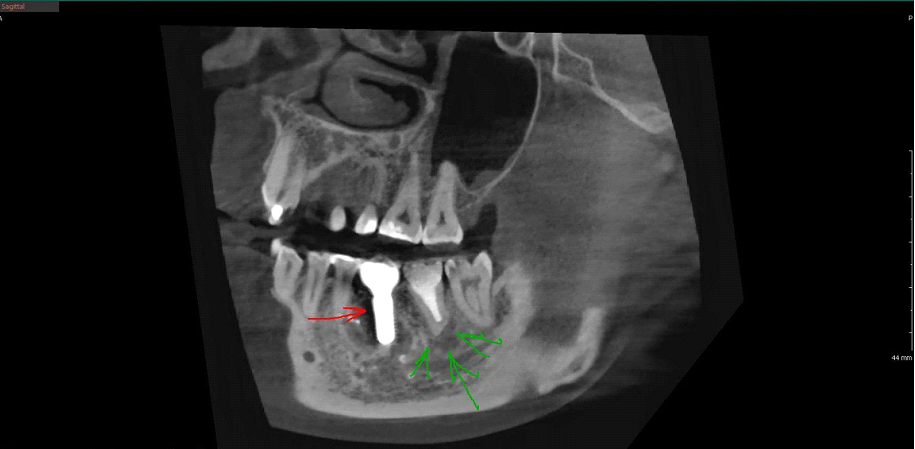

Вот тот же пациент через 4 месяца, под зелёными стрелками заметное уменьшение площади костного дефекта, видны первые признаки успешности зубосохраняющего лечения. Под красной стрелкой имплантат, установленный в момент удаления зуба: